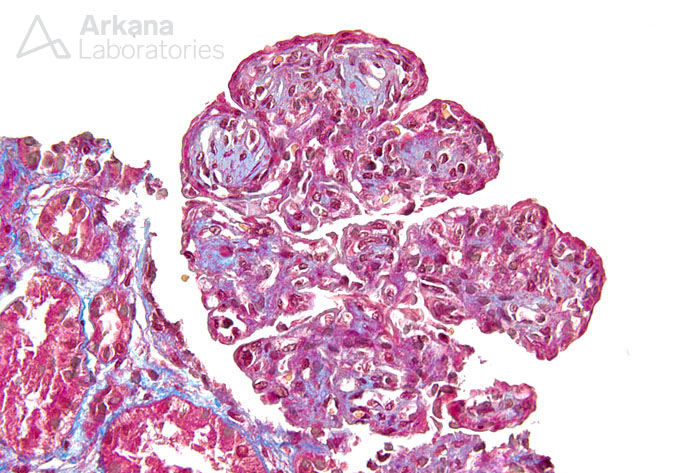

Previous Image Next Image Mesangioendocapillary Proliferation with Lobular Accentuation_3 Like Loading...